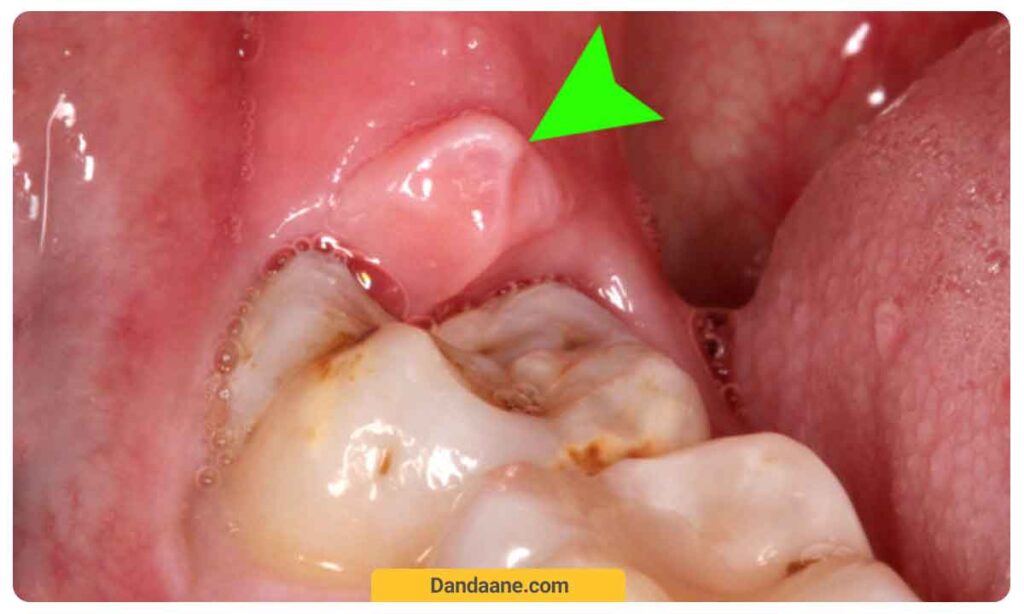

افراد در سنین 10 تا 30 سالگی با رویش دندان عقل مواجه می شوند. در اغلب مواقه دندان عقل برای رشد جای کافی ندارند و به طور ناقص رشد می کنند. زائده ای که به عنوان کیست دندان عقل شناخته می شود در واقع چیز متفاوتی نیست و تنها به عنوان فولیکولی که بر روی تاج دندان عقل شکل می گیرد، به دلیل اندازه بزرگتر دندان عقل نسبت به سایر دندان ها، طبیعتا ابعاد بیشتری دارد. آسیب های ناشی از این کیست می توانند شامل درد، التهاب، تورم، عفونت و حتی شکستگی در فک باشند. بنابراین، در صورت تشخیص مشکل در دندان عقل، بهتر است به سرعت به دندانپزشک متخصص مراجعه کنید. در ادامه عکس کیست دندان عقل را مشاهده خواهید کرد.